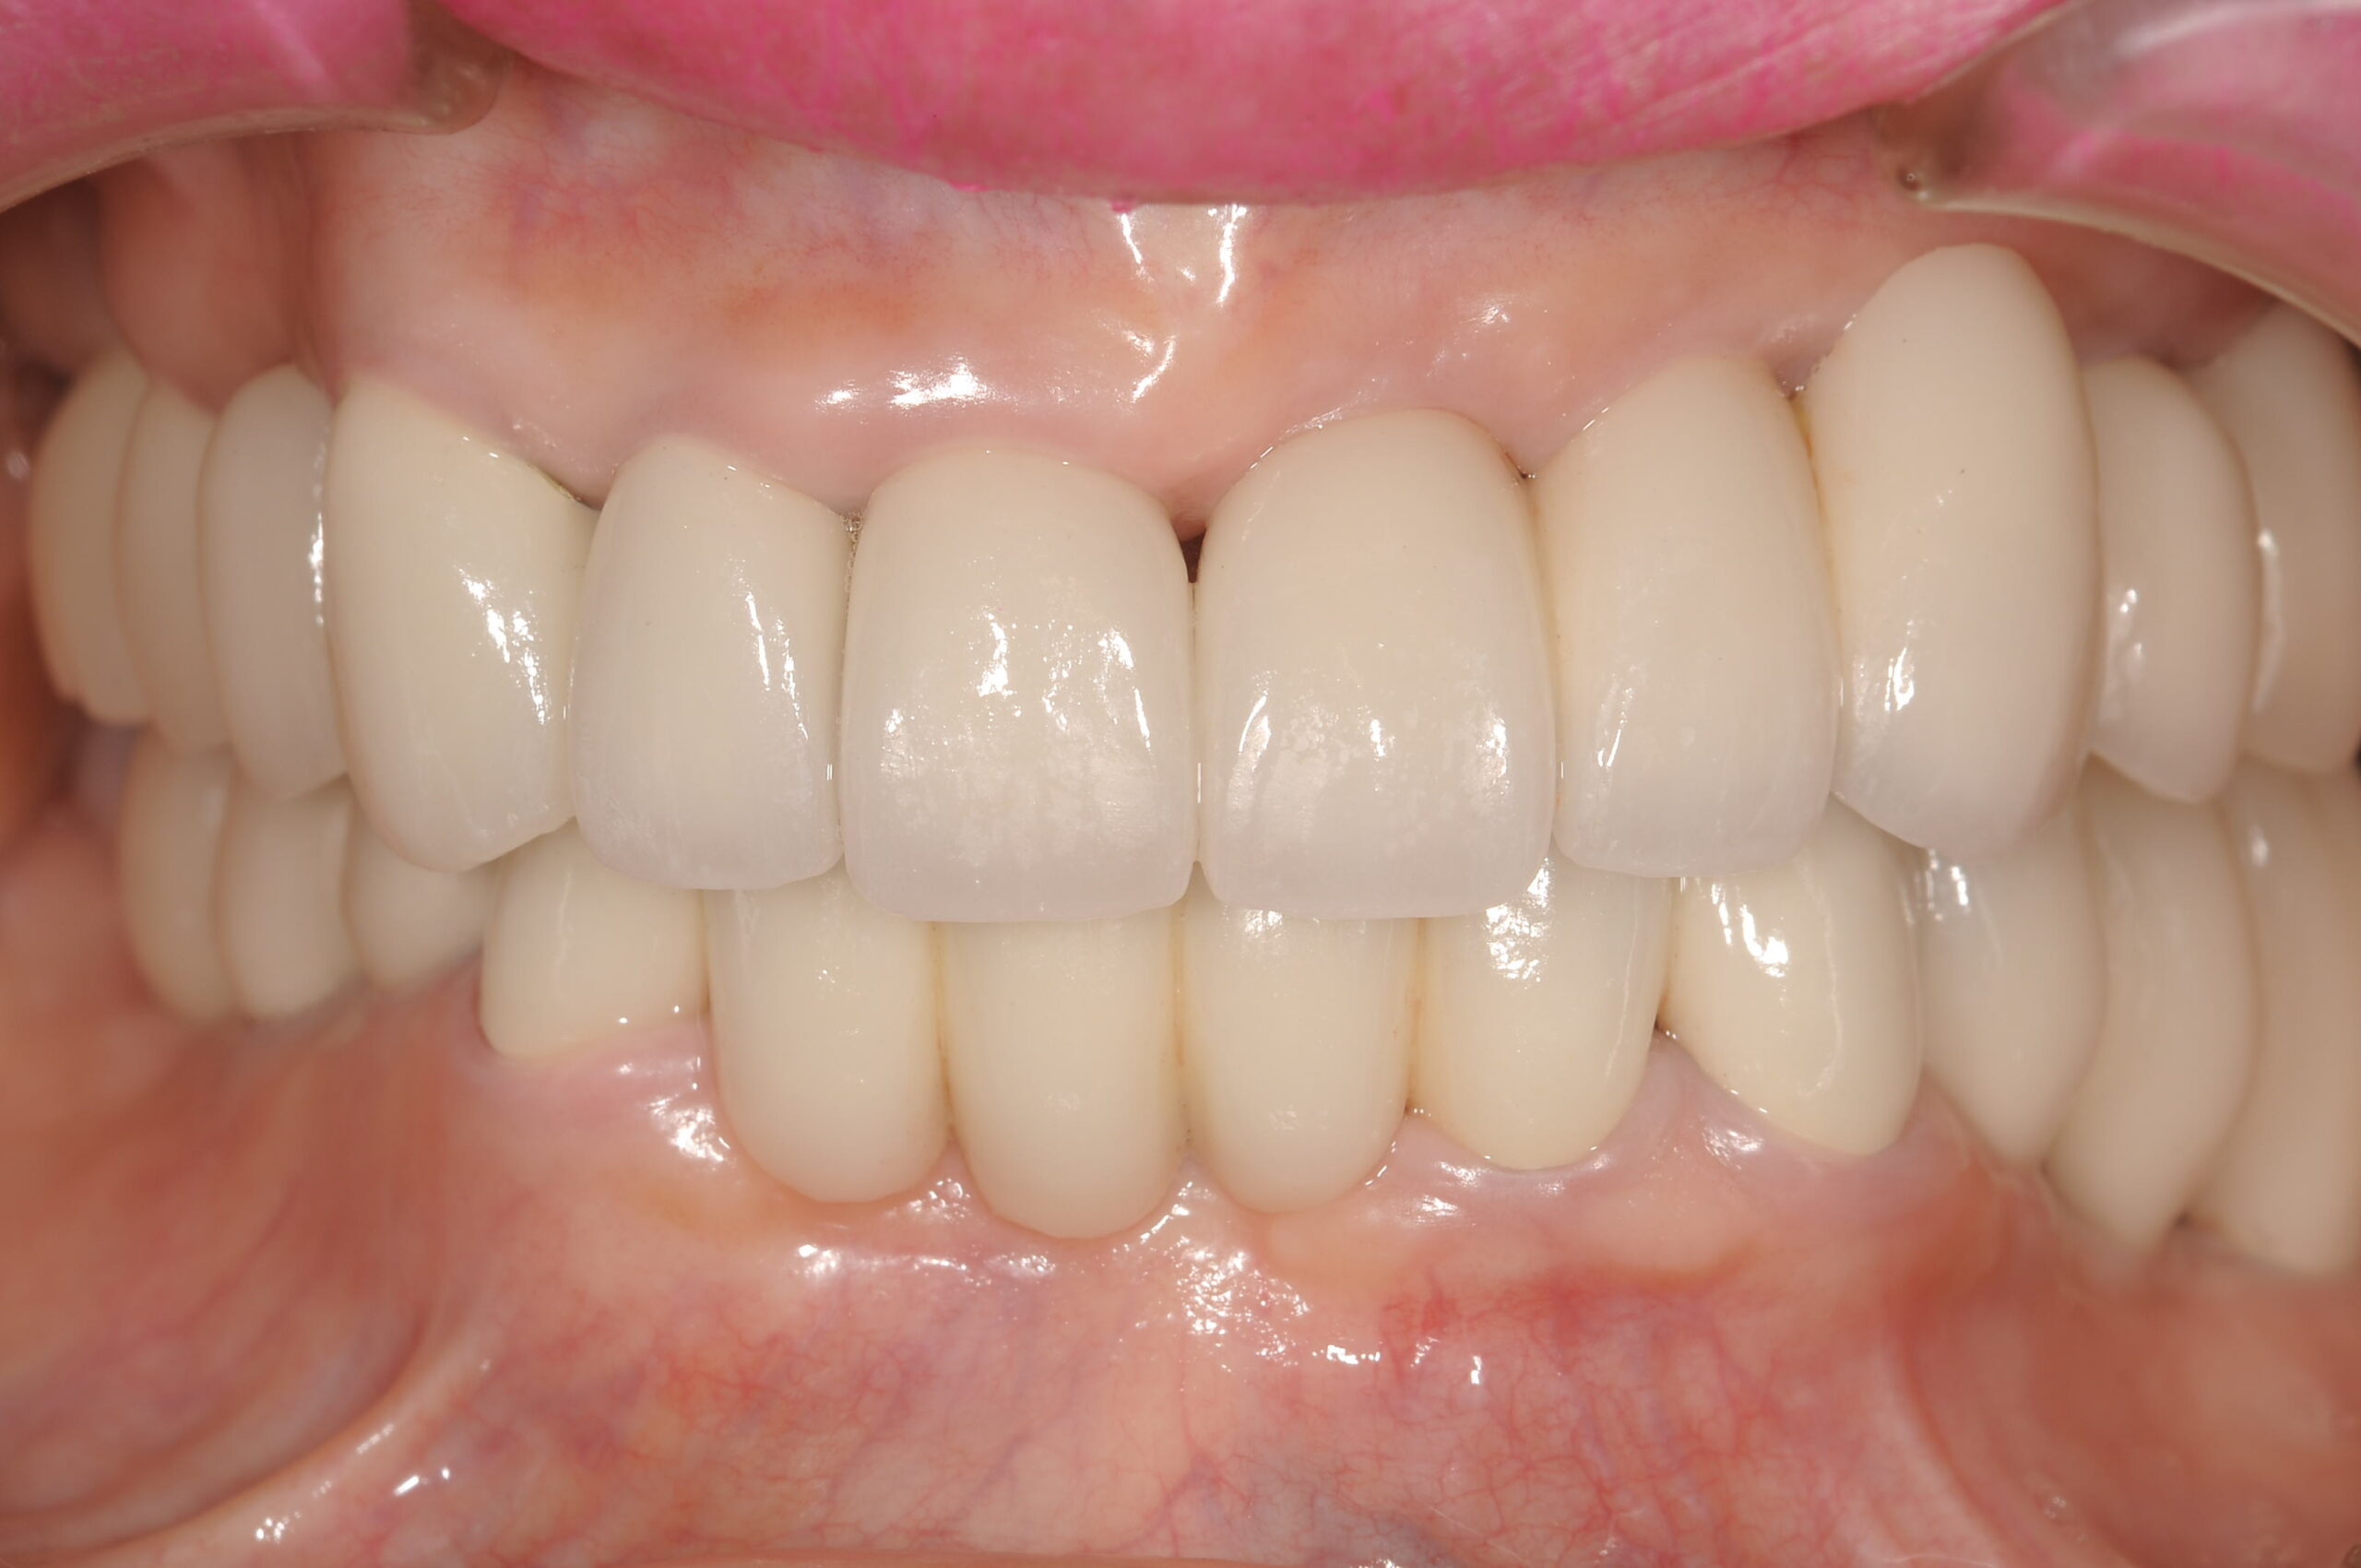

上顎の12本,下顎12本の固定式の歯が入り、なんでもおいしく食べられるようになられました。